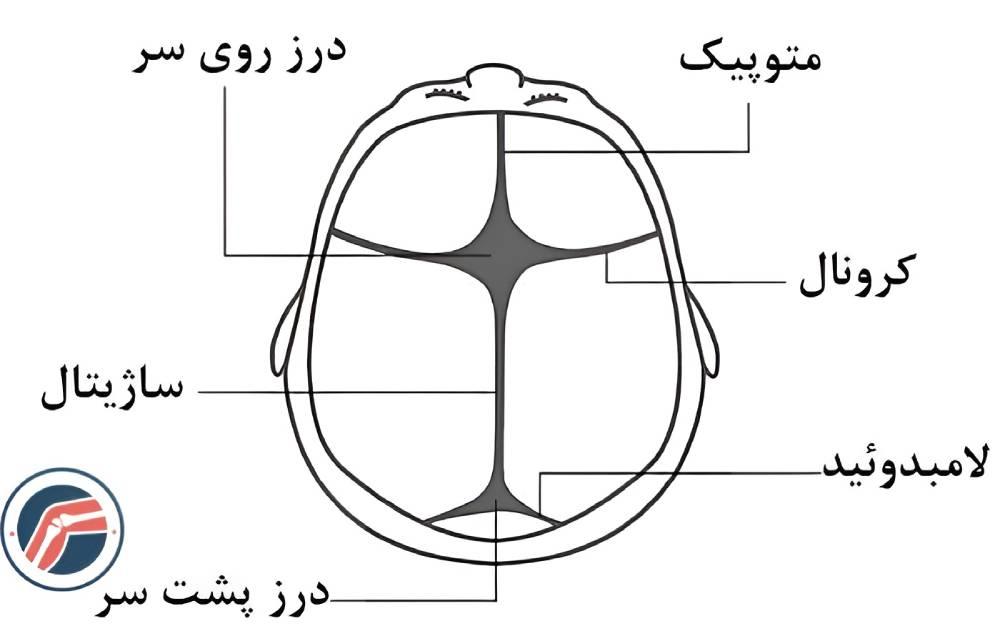

کرانیوسینوستوز یا بدشکلی سر در نوزادان یک اختلال مادرزادی است که به علت اتصال زودتر از موعد طبیعی استخوانهای جمجمه ناشی از بسته شدن زودهنگام درزهای جمجمه در نوزادان بوجود میآید. در یک نوزاد تازه متولد شده، استخوانهای قسمت بالای جمجمه توسط درزهایی از هم جدا شدهاند، این درزها ساژیتال (Sagittal)، کرونال (Coronal)، متوپیک (Metopic) و لامبدوئید (Lambdoid) نام دارند که در شکل زیر مشخص شدهاند.

به دلیل وجود این درزها عبور نوزاد از رحم مادر در هنگام تولد راحتتر انجام میشود و رشد جمجمه به موازات رشد مغز امکان پذیر میشود. این درزها نباید تا زمان تکمیل شدن پروسه رشد تا بعد از نوجوانی بسته شوند، بجز درز متوپیک که معمولا به طور طبیعی در سال اول زندگی بسته میشود. هنگامی که یک یا چند درز جمجمه زودتر از زمان طبیعی بسته شود، همزمان با رشد مغز، جمجمه فقط میتواند در جهت درزهای بسته نشده رشد کند که این باعث بدشکلی سر کودک میشود. این اختلال از هر ۲۵۰۰ نوزاد در یک نوزاد رخ میدهد.